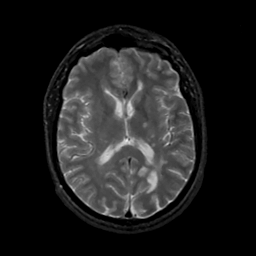

MR Study #14, June 2, 1991 -- Slice #28

[Home][Help][Clinical][Tour 1][Tour 2] Slice 28